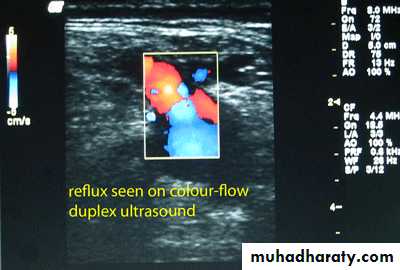

Duplex in varicose veins